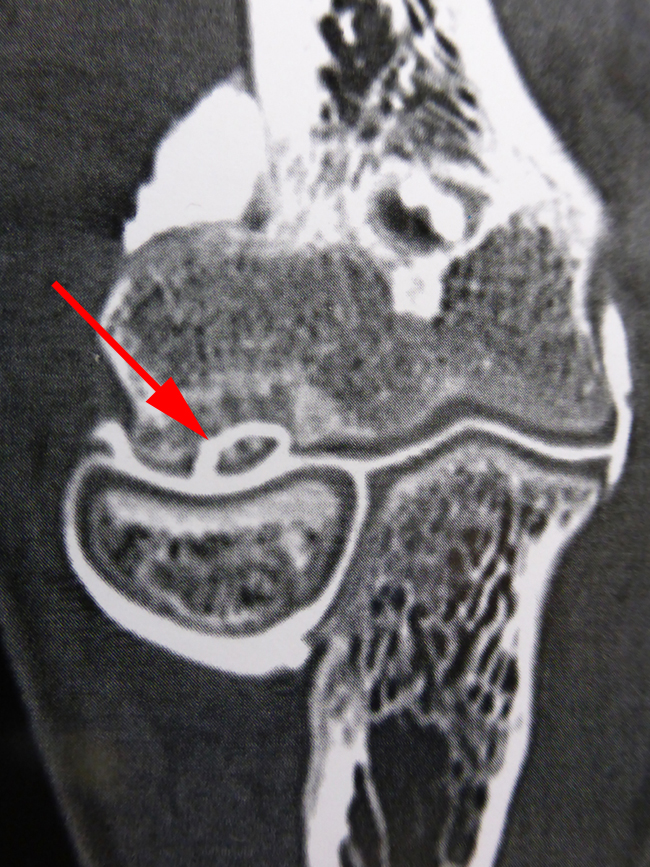

Les radiographies font le diagnostic en montrant un « trou » dans l’os, presque toujours au même endroit, à l’extrémité de l’humérus en regard de la cupule radiale.

Ce fragment libre dans le coude provient d’une ostéochondrite.

Il est facilement enlevé sous arthroscopie.